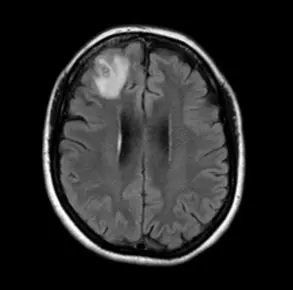

A 씨의 진단명은 광동주혈선충증이었다. ‘쥐 폐선충’으로도 알려진 이 감염병은 광동주혈선충의 중간숙주(조개 등의 담수산 패류와 민달팽이)나 운반숙주(새우, 게, 개구리 등)를 덜 익혀 먹을 경우 감염된다. 때로는 유충으로 오염된 채소를 섭취하거나 물을 마시는 경우에도 감염될 수 있다.

쥐 폐선충의 초기 증상은 구역, 구토, 복통 등이며 두통, 발열, 근육 통증, 피로, 불면증 및 신경학적 증상이 나타날 수 있다. 목 경직과 통증, 피부의 따끔거림이나 타는 느낌, 복시, 배뇨 또는 배변 어려움, 발작 등이 동반될 수 있다. 어린이의 경우 발열, 무기력, 위장 통증, 근육 경련, 경련 및 사지 약화 등의 증상이 나타날 수 있어 주의해야 한다.